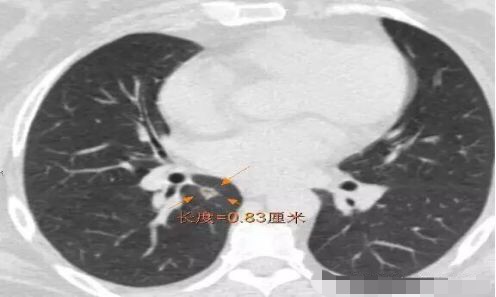

病例1 .

2014年 首次发现右肺上叶GGO,病灶直径8.3毫米, 2016年复查发现右肺上叶GGO,病灶直径12.4毫米。2年大约生长4毫米,平均1年生长2毫米。2016年手术病理结果:浸润性腺癌。

2014年 病灶8.3毫米